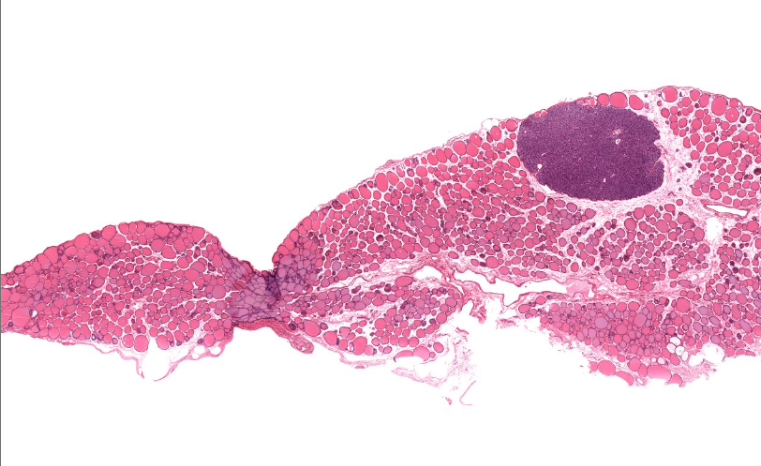

mammary gland

has many open holes, of varying sizes

has very light pink in open holes

produces milk